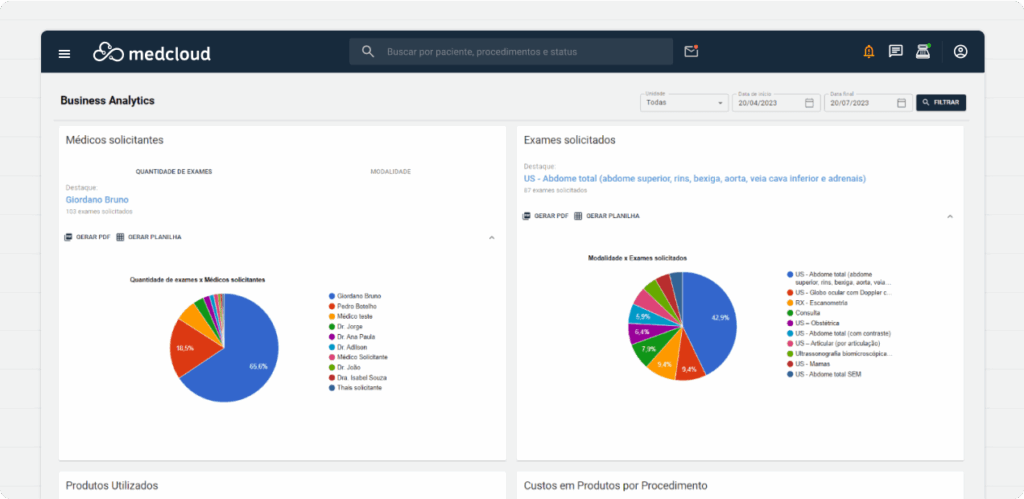

Exporta la información de todos los gráficos en formato XLS o PDF para trabajar con ellos como prefieras.

Cree nuevas estrategias de productividad con el gráfico de inactividad de la sala.

Cada gráfico fue diseñado para entregar información compleja de una manera simple y precisa.